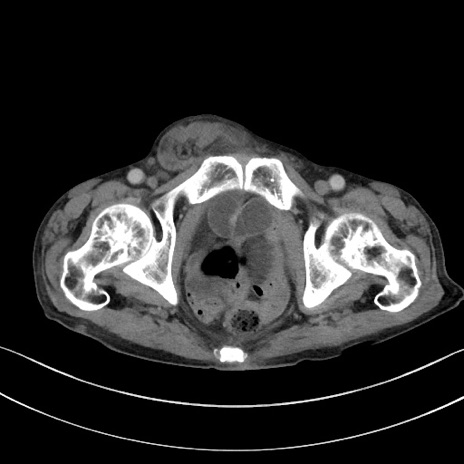

症例3(横断像)

【症例】 70歳代男性

【主訴】右鼠径部腫瘤、疼痛

【現病歴】本日朝より上記主訴あり、受診。

【既往歴】膀胱癌にて膀胱全摘、両側尿管皮膚瘻

【データ】WBC 5600、CRP 0.56